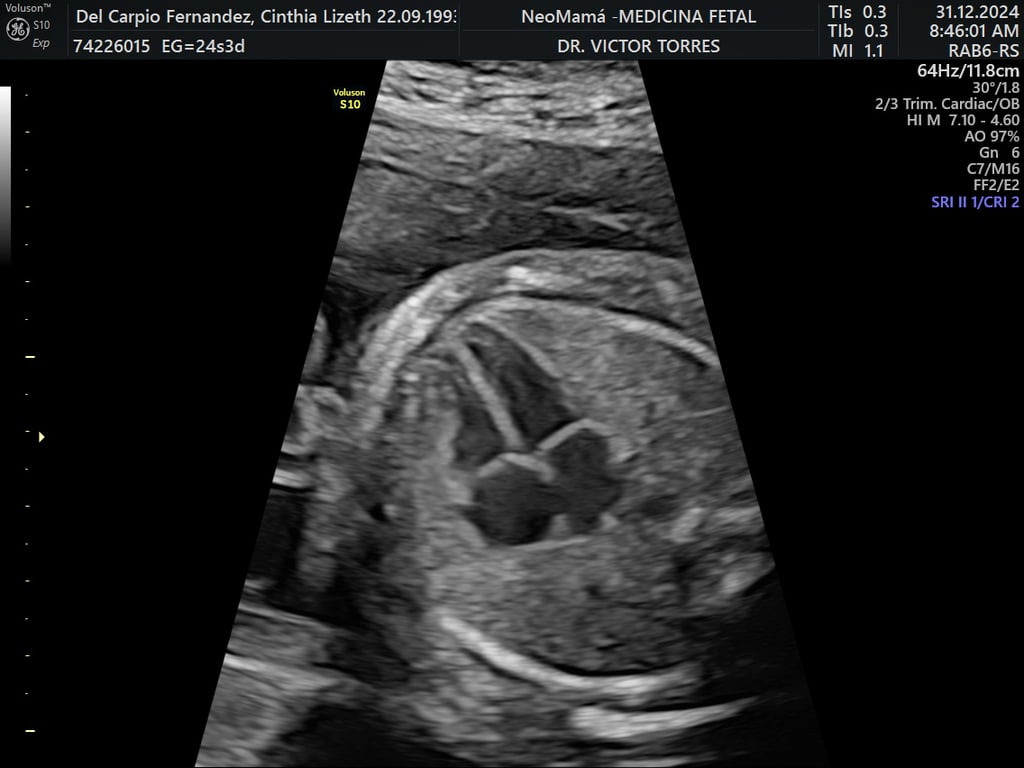

ecocardiografía fetal